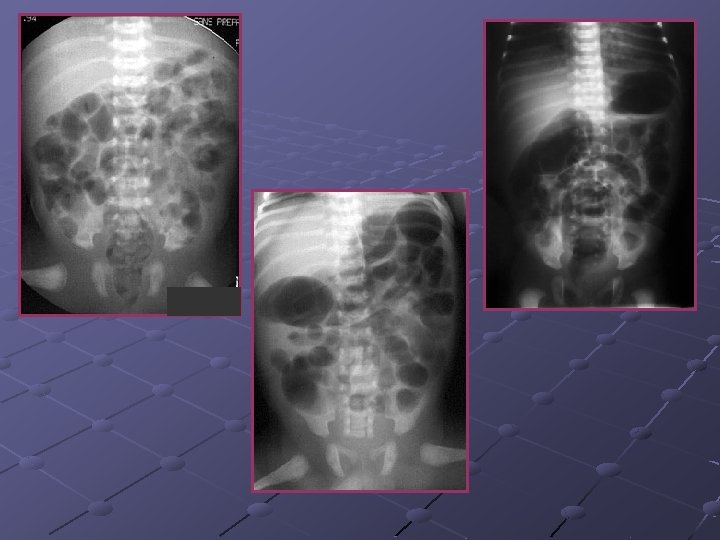

Cas n° 5 17 mois Histoire médicale antérieure = o Pleurs, douleurs abdominales

3, 7 x 2, 8 cm Depuis le rectum hypochondre gauche

INVAGINATION INTESTINALE AIGUE (IIA) Télescopage et penetration d’ un segment intestinal dans le segment d’ aval. Urgence diagnostique et thérapeutique: compression vasculaire ischémie et nécrose Nourrisson ( 80 % entre 6 mois et 2 ans ). Maximum entre 4 et 12 mois (I). Avant 3 mois ou après 5 ans (II). Prédominance masculine ( 3 G/2 F).

Idiopathique ( 90% des cas ): adénolymphite mésentérique(caractère saisonnier ) Secondaire: lymphome digestif, meckel, duplication digestive , polype , purpura rhumatoïde , troubles fonctionnels post chirurgicaux , impactions digestives ( mucoviscidose. . ) Formes anatomiques: iléo-iléale n iléo-colique n Appendico-colique n colo-colique n diam. boudin < 20 mm diam. boudin > 25 mm Diagnostic = échographie et non l’ASP Traitement: - Lavements (air, hydrosoluble, eau) - Chirurgie Contre-indications des lavements: péritonite, choc